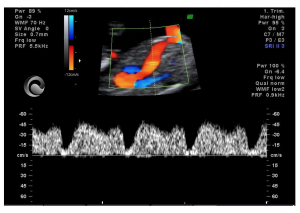

Correcta evaluación del flujo sanguíneo a través de la válvula tricúspide del corazón fetal entre las 11-13 semanas